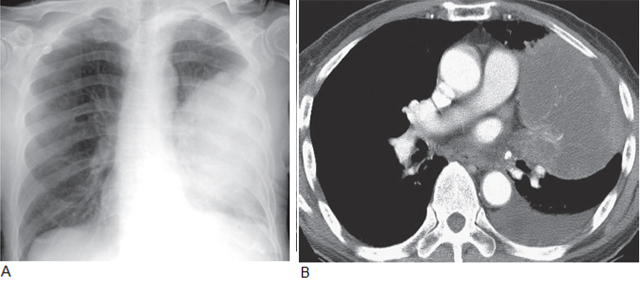

图2 鳞状细胞癌伴空洞

A. 胸片显示右上叶大的厚壁空洞;B.CT 显示厚壁空洞及壁结节,为恶性空洞的典型征象,属T2 期

图3 大细胞肺癌

A. 胸片显示左肺巨大肿块;B. 在对比增强CT 上,巨大肿块占据左肺,左侧胸腔可见积液